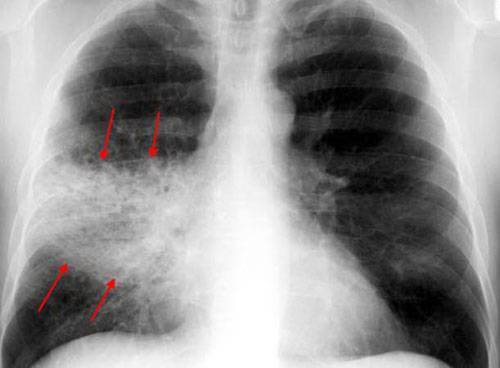

Самостоятельно по визуальным признакам определить вид пневмонии, бронхита, гриппа, туберкулеза невозможно, необходимо пройти рентген обследование. Характерные особенности легочных заболеваний:

От других лёгочных патологий бронхиты отличаются в первую очередь областью локализации воспалительного процесса. При этом заболевании поражается слизистая оболочка бронхов, тогда как у больного пневмонией затрагиваются альвеолярные участки лёгких. На рентгене очаги бронхита чаще всего визуализируются слабо.

- Результаты рентгенологических исследований не обнаруживают патологии в легких;